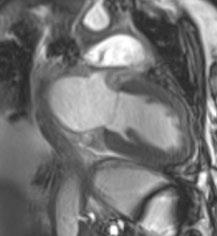

Receive our free newsletters and alerts Get the latest updates on all our upcoming journals and receive first-class insights into ground-breaking news and advancements in medicine across multiple therapeutic areas. www.emjreviews.com Join our mailing list

Turn static files into dynamic content formats.

Create a flipbook